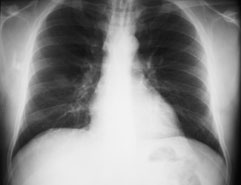

Ein 41-jähriger Mann sucht Sie auf, weil er zum dritten Mal in diesem Winter erkältet ist und dieses Mal sogar mit Fieber. Er gibt ausserdem an, etwas trockenen Husten zu haben. Ausserdem besteht seit Wochen eine Sinusitis, die nicht so recht abheilen will.

Gewichtsverlust wird verneint. Der Patient ist Nichtraucher und fühlte sich bis anhin gesund.

Die Lungenperkussion und -auskultation ist unauffällig. Das Labor zeigt eine Leukozytose ohne Linksverschiebung und ein CRP von 97 mg/dl. Hier das Röntgenbild der Lunge:

Thorax pa

Welche Befunde fallen Ihnen auf?

Es ist klar, dass aufgrund dieses Befundes keine Diagnose gestellt werden kann. Welche Diagnose ist aufgrund der Klink und des radiologischen Befundes am wahrscheinlichsten?